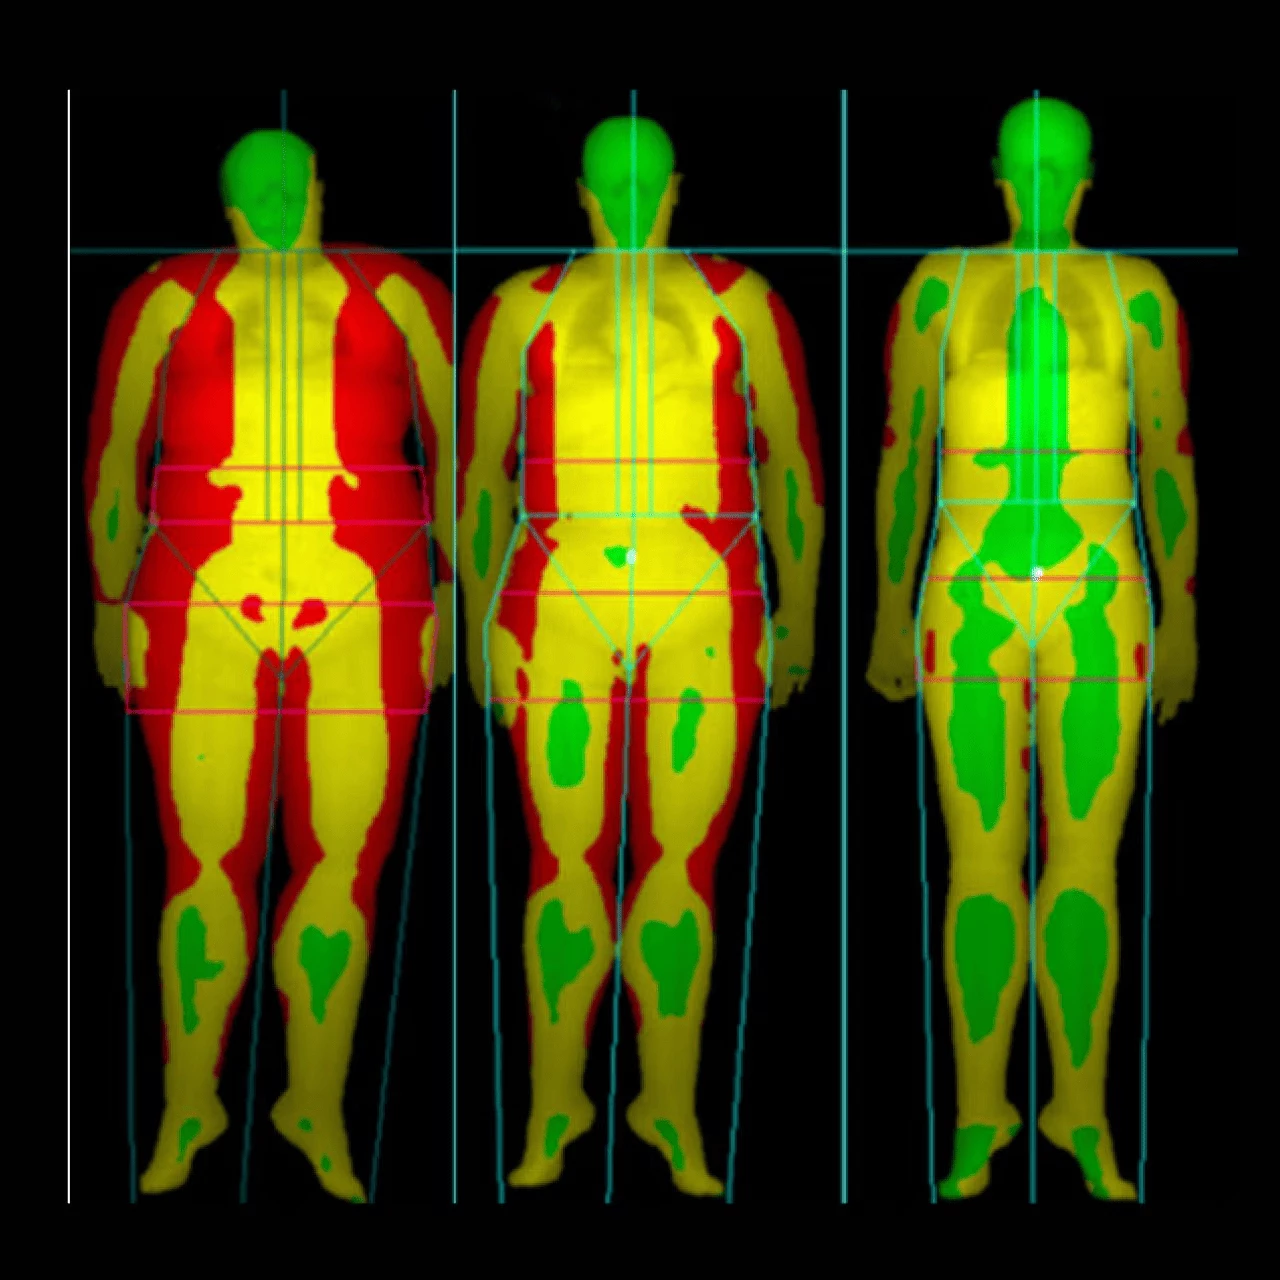

Hệ thống đo loãng xương toàn thân

Hệ thống đo mật độ xương (BMD) hiện đại của hãng giúp chẩn đoán bệnh loãng xương

Tích hợp phần mềm tính toán nguy cơ gãy xương trong 10 năm tới

Đo khối lượng mô nạc và mô mỡ, bao gồm tỷ lệ phần trăm mỡ để đánh giá thành phần cơ thể và giúp hiểu rõ nguy cơ sức khỏe chuyển hóa